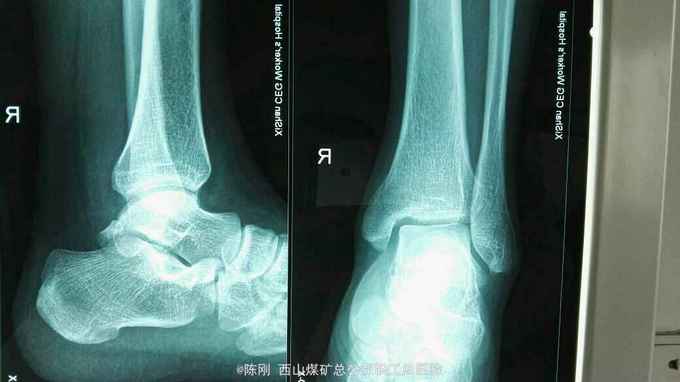

复查x线片

左外踝毁损伤,左肱骨脱位半大结节骨折,左内踝骨折,右内,后踝骨折